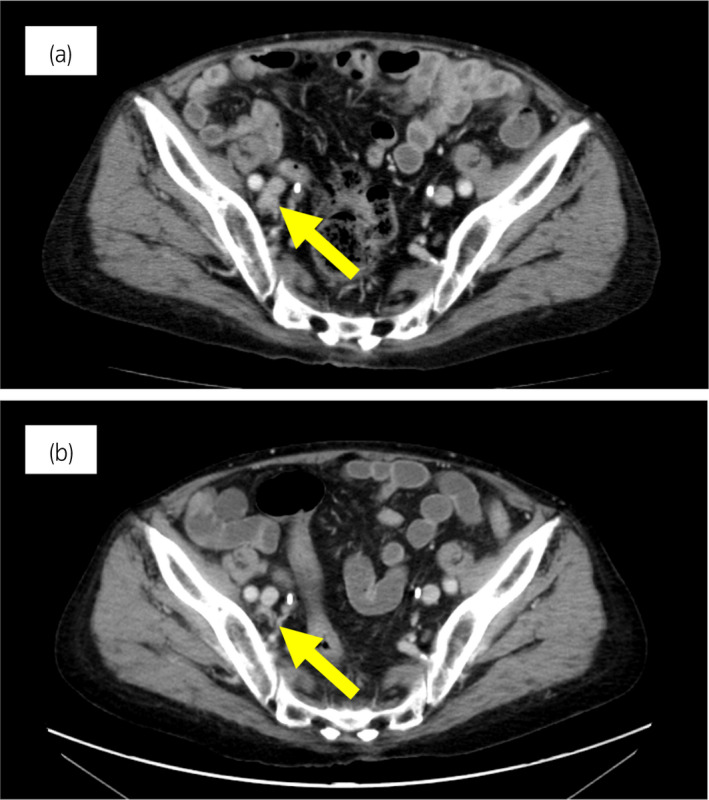

病例1

70 岁男性被诊断为转移性 PC,cT3bN1M1b,Gleason 评分(GS)为 4 + 5 = 9,前列腺特异性抗原(PSA)水平为 40.8ng/ml,3 年前伴有胸椎转移。 对前列腺进行联合雄激素阻断 (CAB) 治疗和质子放射治疗 (78.0Gy/39fr)。 PSA 水平降至 <0.01ng/ml,CAB 在 2.5 年后停止。 停止 CAB 五个月后,他出现背痛,PSA <0.01 ng/ml。 计算机断层扫描 (CT) 扫描检测到多处肝、骨和淋巴结转移,神经元特异性烯醇化酶 (NSE) 水平高达 171ng/ml(图 1a)。 骨转移活检显示神经内分泌前列腺癌 (NEPC) 的诊断(图 2),患者被转诊至佳学基因合作医院。 内分泌肿瘤精准治疗医生用顺铂、依托泊苷和亮丙瑞林治疗。 第三个疗程后,转移部位明显缩小(图 1b)。 顺铂和依托泊苷治疗 1 年,但患者因神经病变要求停药。 他开始服用恩杂鲁胺。 治疗 3 个月后,患者出现背痛和左锁骨下淋巴结肿大(图 3a)。 肝转移保持不变,顺铂治疗后缩小。 通过肿瘤精准用药850基因检测证实了 BRCA2 突变。根据基因检测结果,主治肿瘤科医生给予了奥拉帕尼。 三个月后,背痛好转,淋巴结转移缩小,确定为部分缓解(PR)(图3b)。 肝转移灶保持不变。

图1:病例1.顺铂和依托泊苷三个疗程前后的腹部CT图像。 (a) 治疗前和 (b) 治疗后。